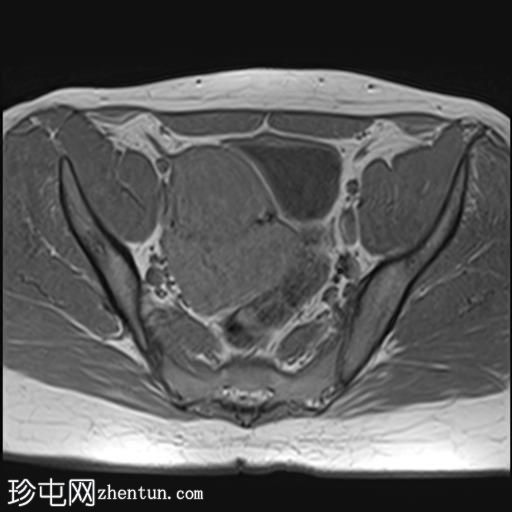

轴位

T2加权像

盆腔内可见多个边界清晰的肿块:

其中一个位于子宫上方,T2加权像呈中等信号,中心区域呈高信号,增强T1脂肪抑制像未见强化。右侧卵巢增大,增厚的血管蒂扭曲,未见强化,轴位和矢状位T2加权像均显示清晰。

另一个位于子宫后窝,T2加权像呈中等信号,增强扫描显示明显强化。

轻度腹腔积液